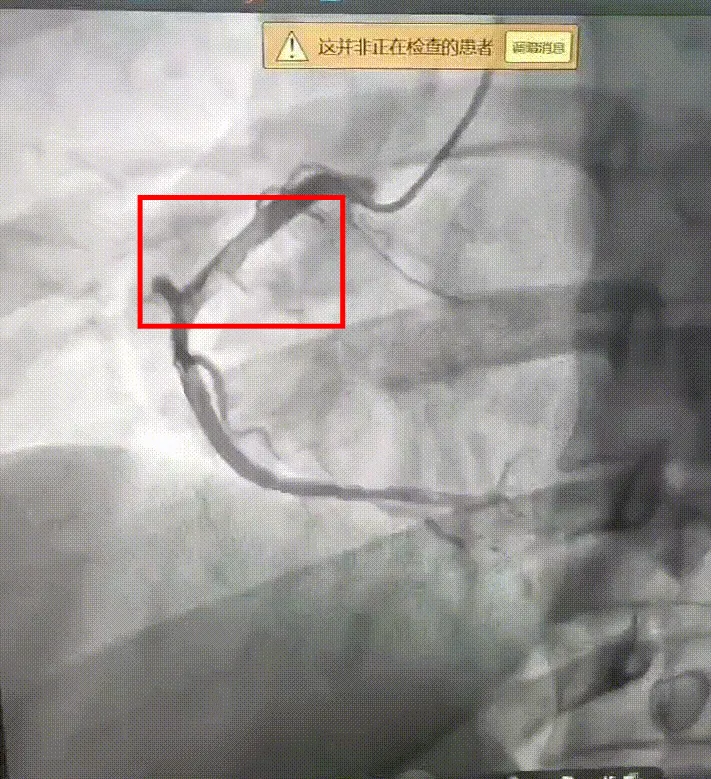

急诊经皮冠状动脉介入治疗(PCI)随即在导管室展开。在血管造影设备的实时引导下,楼善杰精准操作,将指引导管成功送达右冠脉闭塞部位,通过血栓抽吸导管对目标部位进行反复抽吸。操作完成后,堵塞血管的血流成功恢复,手术关键步骤顺利完成。目前,小王已顺利出院。

术后:血栓大部分消失